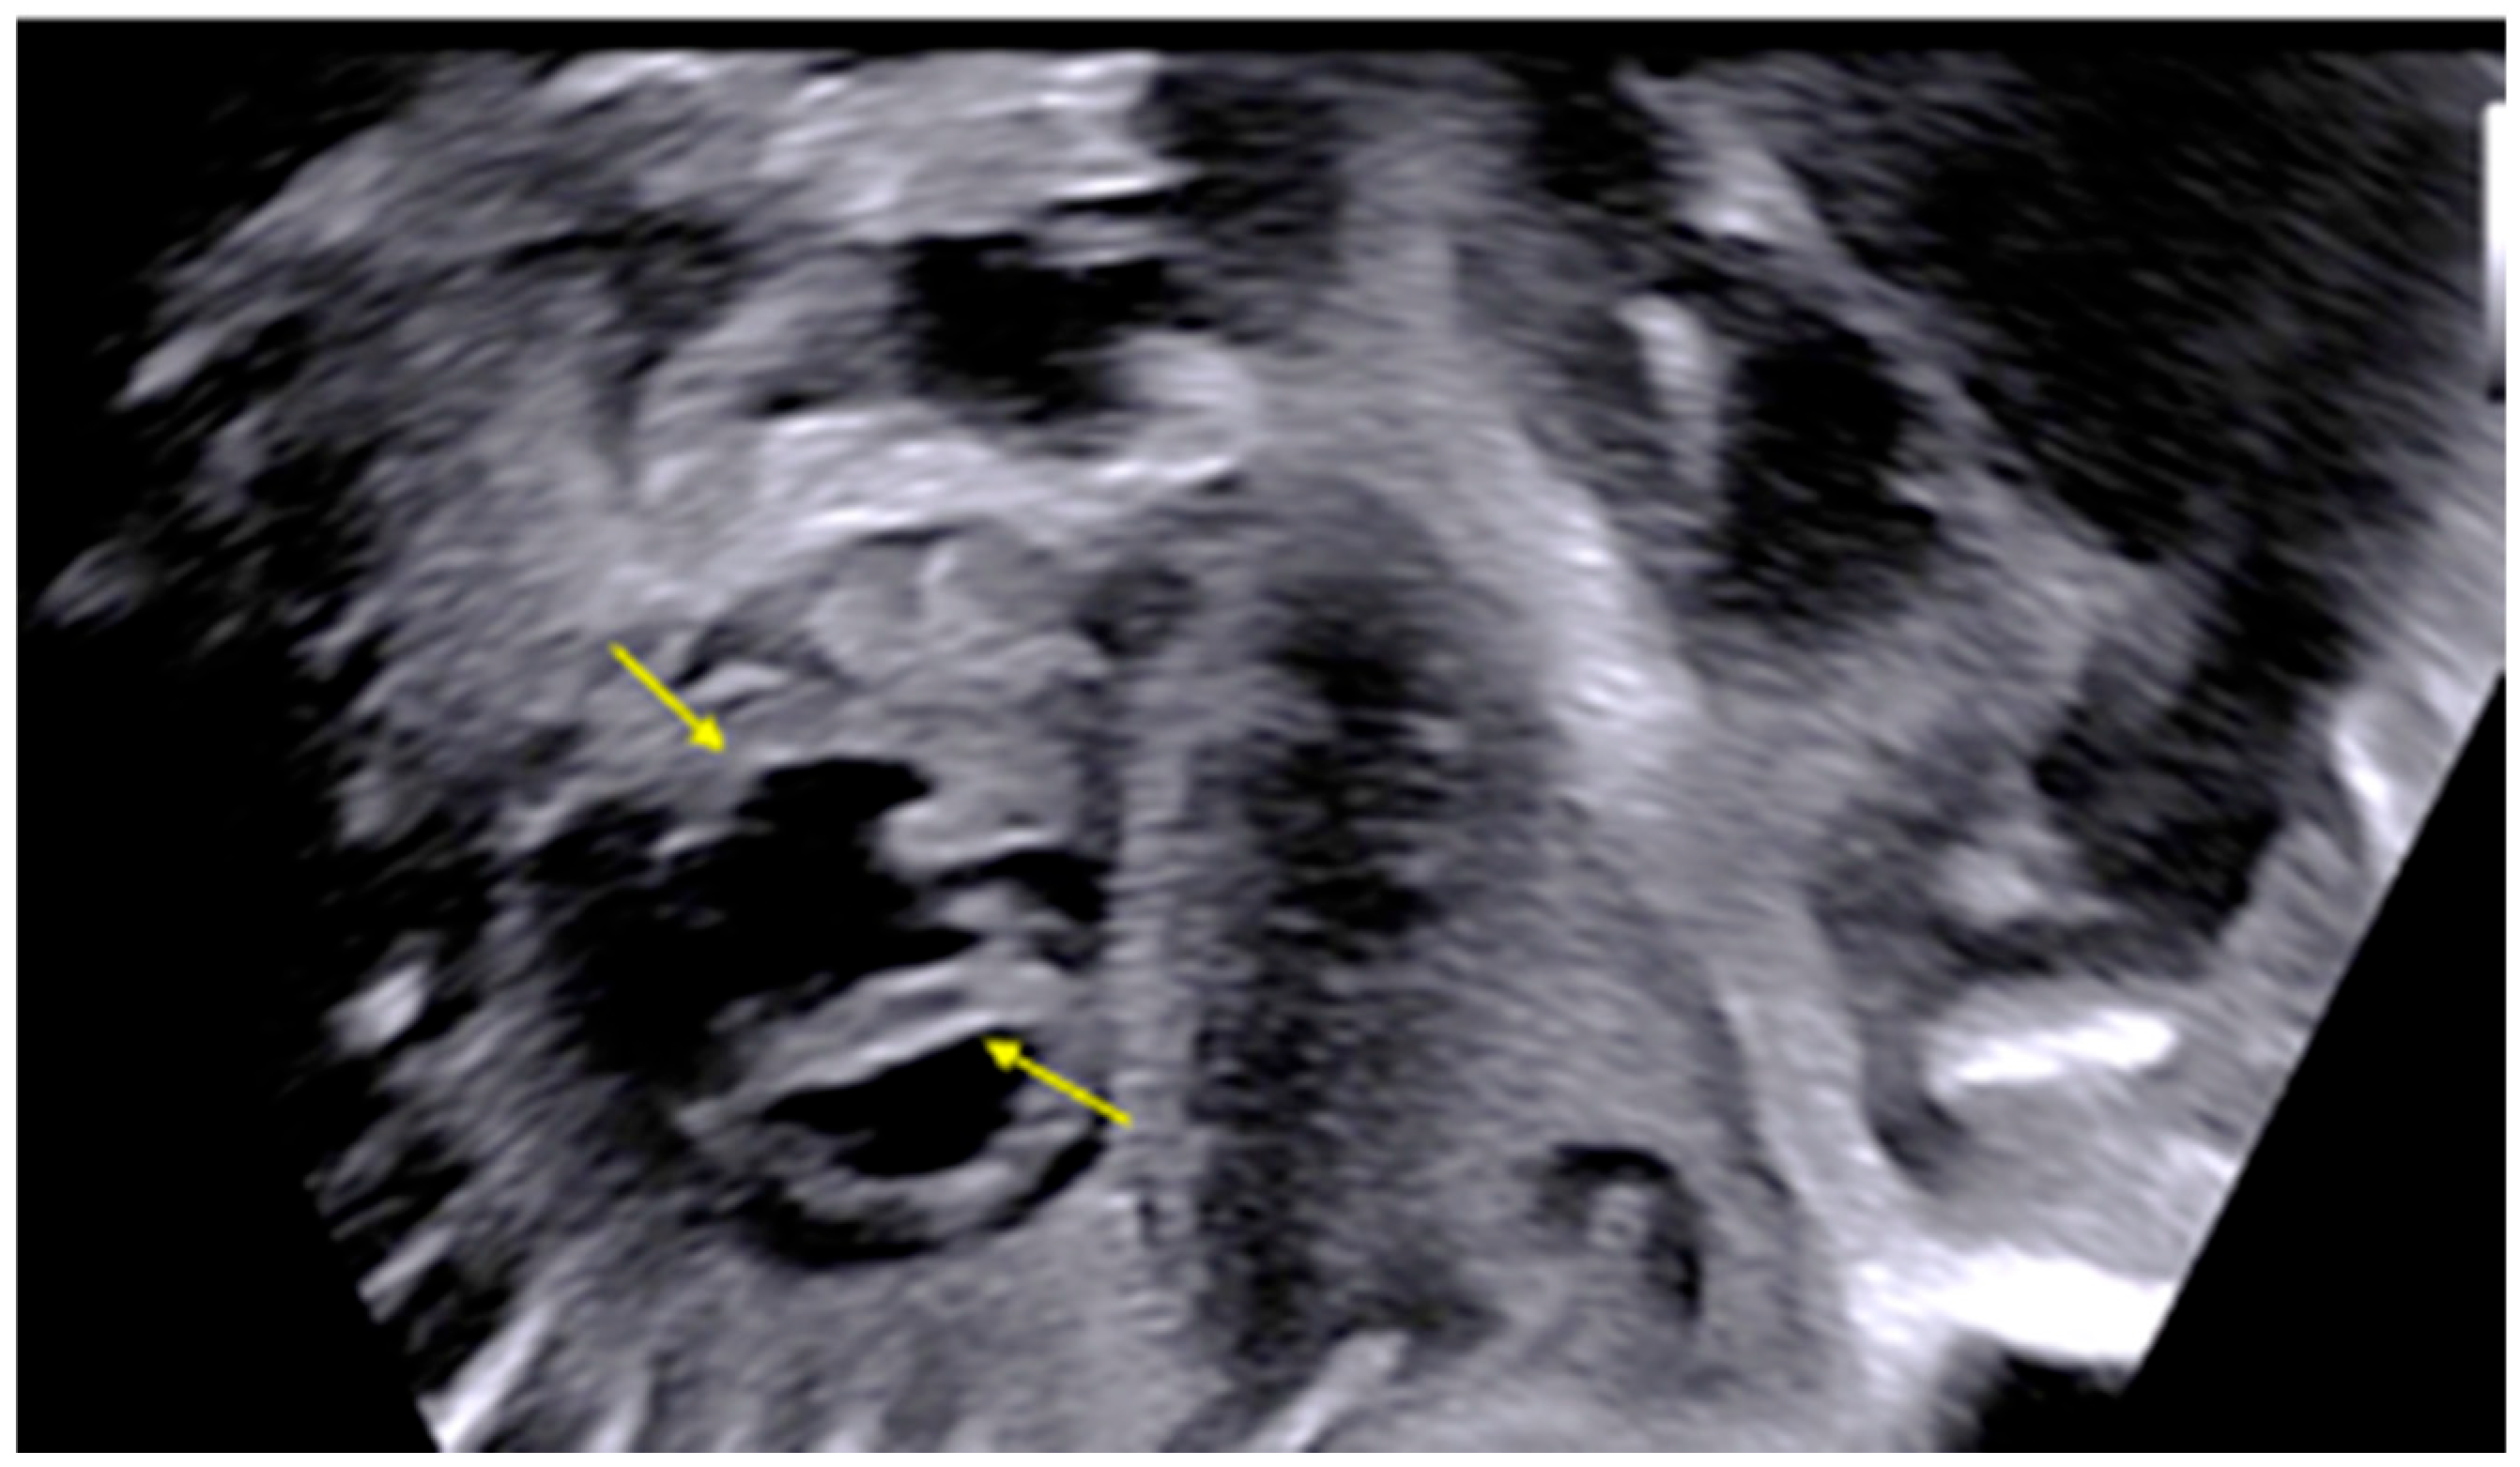

| 28 + 0 | First IVIG cycle (65 g total) | 75 | SF increased to 52%; mild improvement in contractility | Initiated due to signs of fibroelastosis |

| 31 + 2 | Post-IVIG peak response | 70 | SF: 59% (LV), 52% (RV); marked biventricular improvement | Aortic isthmus 3 mm (Z-score –1.65) |